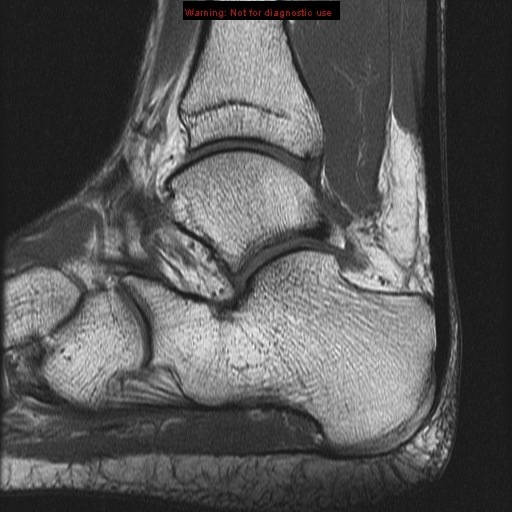

middle subtalar joint

tibiotalar joint

posterior subtalar joint

achilles tendon

achilles tendon anterior subtalar joint

sinus tarsi